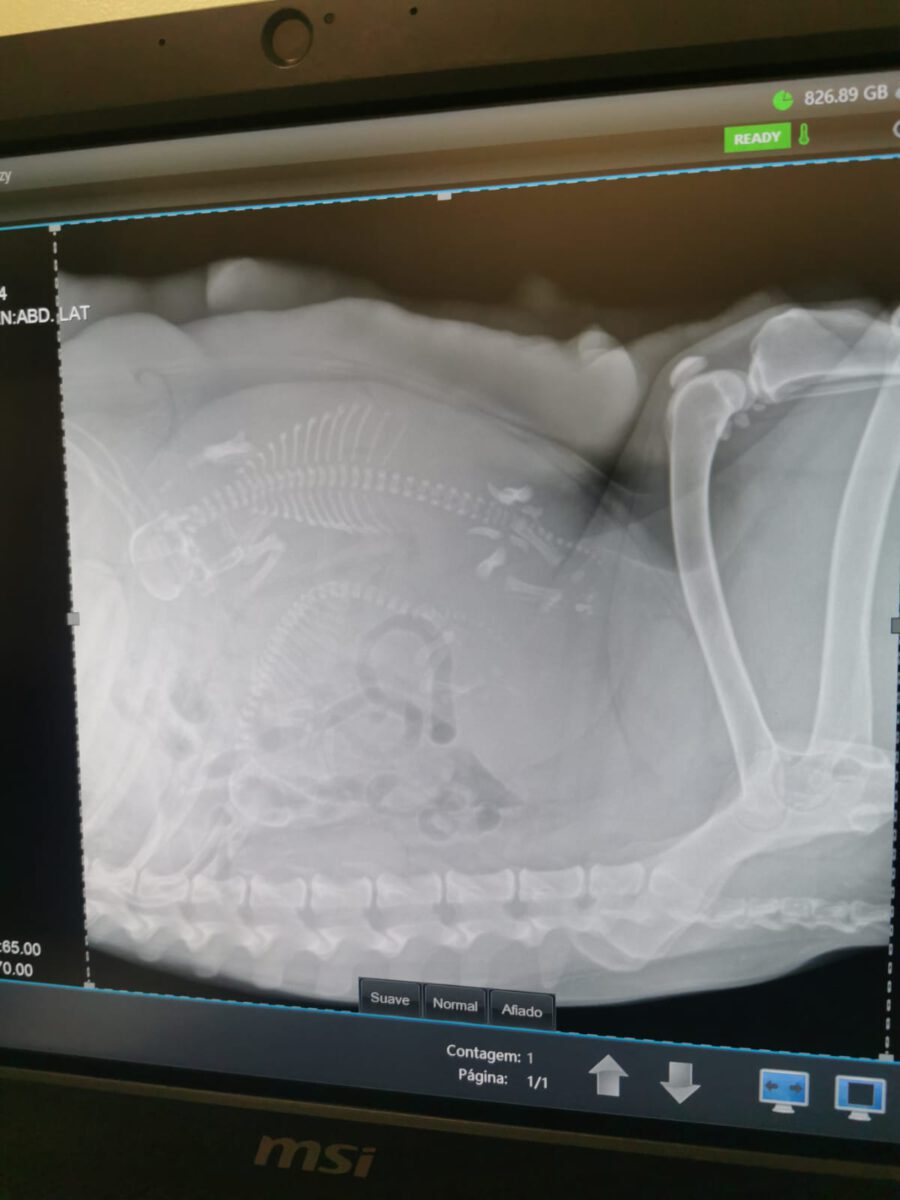

Shenzi lived with her mother (AMORA) and her sister (Gala) on the street or near houses. Dear residents fed the three, but could not take them in the house. They searched for help for a long time and found none. By a happy coincidence they came into contact with our helper Claudia and so we took the three bitches in with us. Unfortunately we came too late because Shenzi and her sister Gala are already pregnant. But at least this will be their last litter of puppies and the little ones will be fine from the start.

Shenzi was a little less fearful than Gala when she was caught and because of the birth she moved in with Elena. In the meantime she has given birth to 8 beautiful puppies and is fully dedicated to her role as a mother. She is now much more open towards Elena and loves to cuddle.